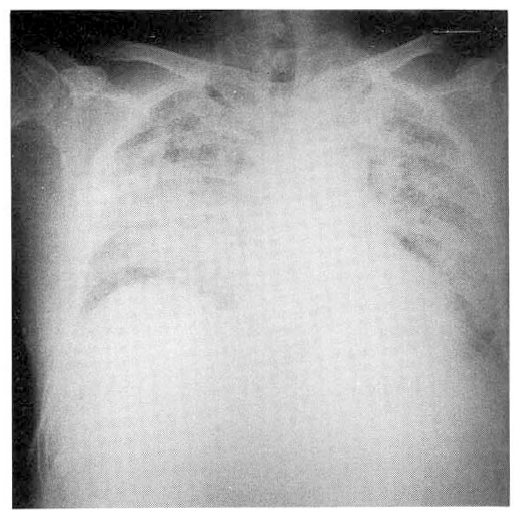

The chest PA at admission showed normal findings (Fig. 1). His laboratory values at admission were leukocyte count, 10,300/mm3; hemoglobin, 11.7g/dl, hematocrit, 35.7%; platelet count, 51,000/mm3; sodium 130mEq/L; potassium 2.9mEq/L; chloride 105mEq/L; calcium 7.7mg%; fasting blood sugar 283mg/dl; 2hours postprandial sugar 310mg/dl; total bilirubin 0.7mg%; GOT 23.6IU/L; GPT 24.9IU/L; alkaline phosphatase 95.0IU/L; total protein 6.3gm/dl; albumin 3.5gm/dl; BUN 14.0 mg/dl; creatinine 0.9mg/dl; and prothrombine time 100%.

Fig. 1.

Chest radiograph on admission shows normal findings.